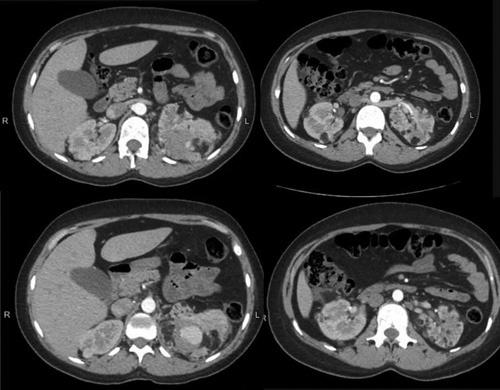

A 29-year-old female presented to the emergency room complaining of right flank pain with an unknown past medical history of tuberous sclerosis. The patient was suspected to have TSD as she fulfilled one of the major features of TSD required to establish a possible diagnosis. On computed tomography scan imaging, bilateral fat-density nodules were revealed in both kidneys. The largest is 7 cm in the left kidney, located at the upper pole, and was associated with a bleeding aneurysm measuring 4 cm in diameter. While the other fatty nodule was recorded at 6 cm in the right kidney at the lower pole.

一名29岁女性因右胁腹疼痛就诊于急诊室,其既往结节性硬化症病史不明。由于该患者符合确立可能诊断所需的TSD主要特征之一,故怀疑其患有TSD。在计算机断层扫描成像中,双侧肾脏均显示出脂肪密度结节。左肾最大的结节位于上极,直径7厘米,伴有一个直径4厘米的出血性动脉瘤。而右肾下极的另一个脂肪结节记录为6厘米。